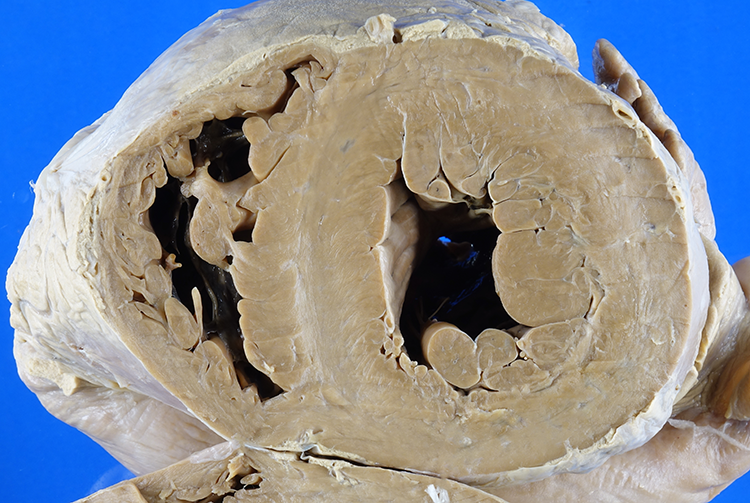

Left ventricular hypertrophy, overall. The interventricular septum measures 2.4 cm in thickness (with the upper range of normal being 1.5 cm).

The patient has aortic stenosis due to calcification of a bicuspid aortic valve (Figure 1), which has led to hypertrophy of the left ventricle (Figures 2 and 3).

Left ventricular hypertrophy, close-up. The interventricular septum measures 2.4 cm in thickness (with the upper range of normal being 1.5 cm).